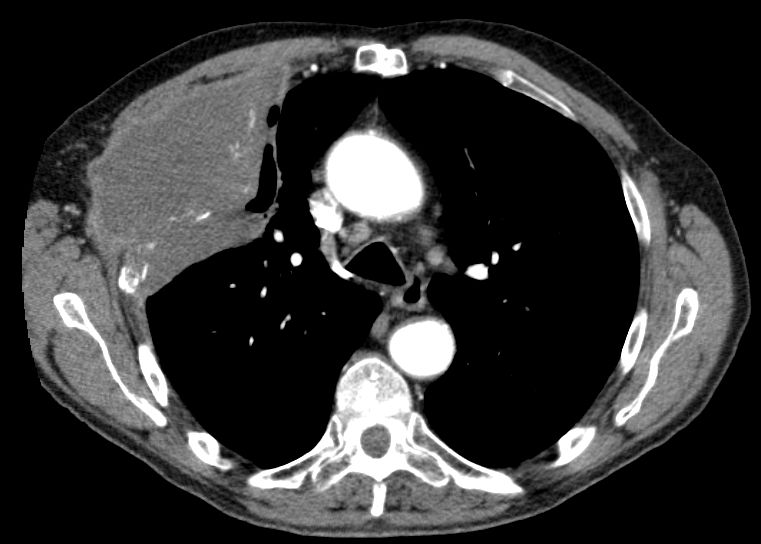

| Embolie | 55-jähriger Mann mit SCC rechts zentral mit

Verschluss der Mittellappens und Stenose des Zwischenbronchus T4 N2b Mo. Vom

Tumor eingeschlossen eine Pulmonalarterie mit einer kreisrunden Aussparung